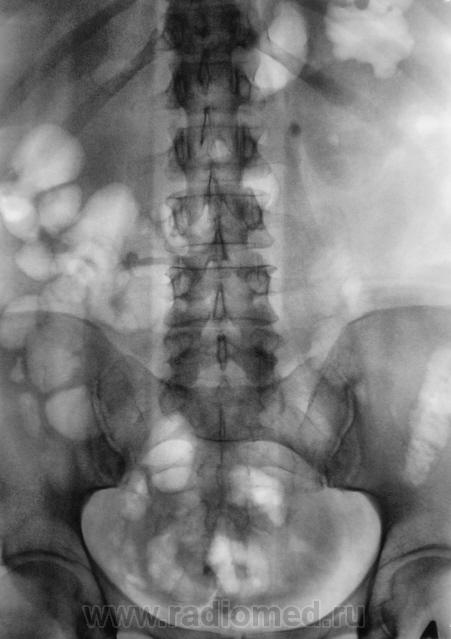

Пациент направлен на внутривенную урографию.

Камень в левом мочеточнике.

В верхней трети.

Мне кажется, неправомочно говорить о камне мочеточника слева, т.к. не видим контрастирования собирательной системы левой почки.Последний снимок выполнен на 15 минуте, конечно надо было выполнить снимки на 40 минуте , а может быть в дальнейшем и позже по времени.

Конечно есть. Да, и "блок" левой почки свидетельствует, да и УЗИ подтвердило.